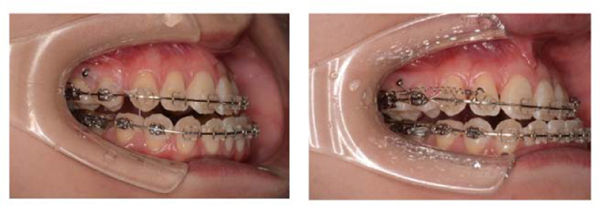

The mandibular third molars (teeth 38 and 48) were extracted under general anesthesia before orthodontic treatment. The mandibular teeth were bonded with preadjusted edgewise brackets (0.022 × 0.028-inch slot), and the mandibular teeth were leveled and aligned using sequential nickel-titanium alloy wires. After extraction of the maxillary first premolars, a 0.022-inch slot preadjusted edgewise appliance was bonded to the maxillary teeth, and leveling and alignment were started using sequential nickel-titanium alloy wires. Next, a miniscrew implant 1.6 mm in diameter and 6 mm in length (Dual-top Auto Screw III; Jeil Medical, Seoul, Korea) was placed in the buccal region between the right maxillary second premolar and first molar (Fig. 4). The maxillary canines were retracted using a 0.016 × 0.022-inch stainless steel wire with elastic chains by application of intrusive force (250 g load). Then the maxillary incisors were retracted using sliding mechanics along a 0.018 × 0.025-inch stainless steel wire with nickel-titanium closed coil springs (250 g load). After presurgical orthodontic treatment for 26 months, orthognathic surgery with BSSO was performed. The mandible was asymmetrically set back 7.0 mm on the right side and 0 mm on the left side. Postsurgical orthodontic treatment was performed for 13 months, and then the fixed appliances were removed after a total treatment time of 3 years and 3 months (Fig. 5), and the patient received a maxillary wraparound retainer and mandibular bonded lingual retainer.